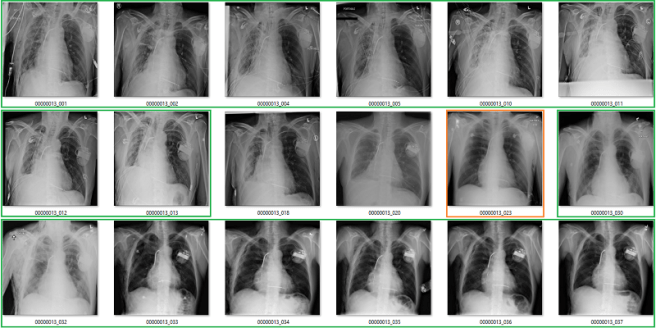

Complete nonsense as far as I can tell. Below are the model predictions, compared against the labels in the dataset. Again, the same technique as earlier for picking images. I’m confident these aren’t cherry picked.

True positives

The green ones are the only actual true positives. The rest have incorrect labels.

True negatives

There are one or two arguable ones in the top 18, but I gave the labels the benefit of the doubt. The red ones in the 2nd 18 are all wrong.

False positives

The red ones are wrong. It also turns out that there are rotated, inverted, distorted, and otherwise abnormal images in the dataset (shown by the red question mark). More on that in the next post.

False negatives

Again, the red ones are wrongly labelled.

Despite an apparent AUC of 0.7 we get really bad classification performance, in line with the label inaccuracy. The model didn’t just ignore the incorrect labels and produce sensible predictions. It was not robust to label noise. Most importantly, the AUC value does not reflect the clinical performance.

This is a huge problem.

This AI system learned to reliably produce meaningless predictions. It managed to learn image features that create the above groups of “opacity” cases with almost no airspace opacities, and “no opacity” cases with big groups of severely abnormal lungs.